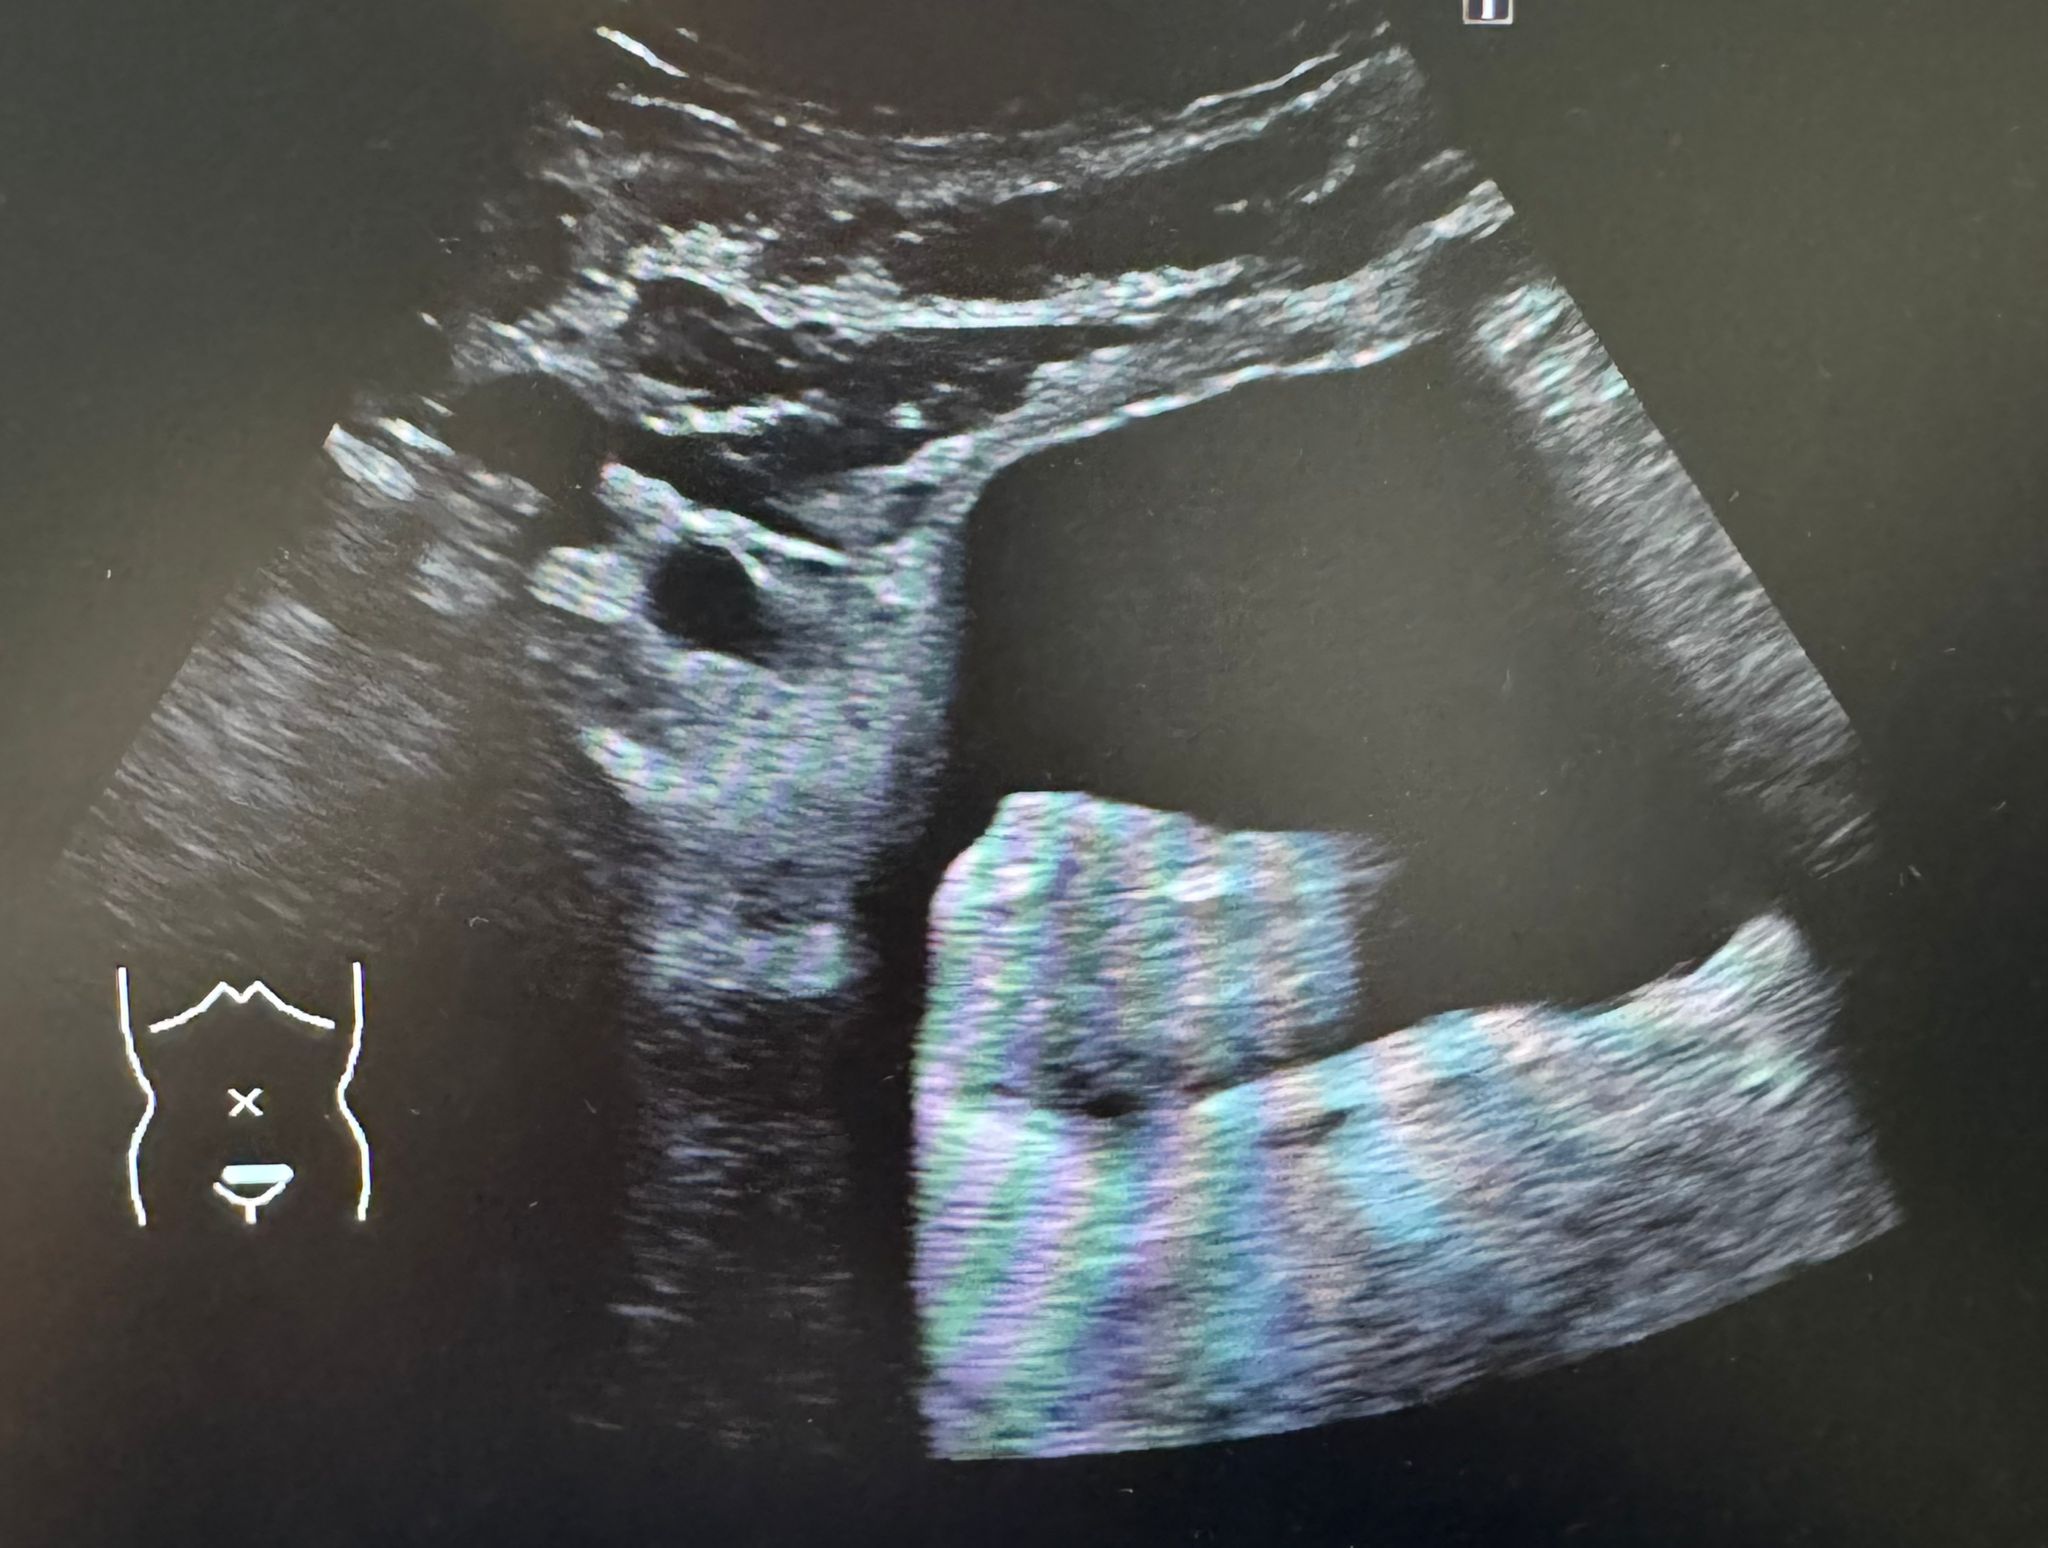

Se realiza ecografía abdominal a pie de cama donde destaca un nódulo heterogéneo y polilobulado a nivel endoluminal vesical, de 4x3 cm, altamente vascularizado. Hígado de tamaño y ecogenicidad normal, no se objetivan LOES. Resto de la exploración sin hallazgos.